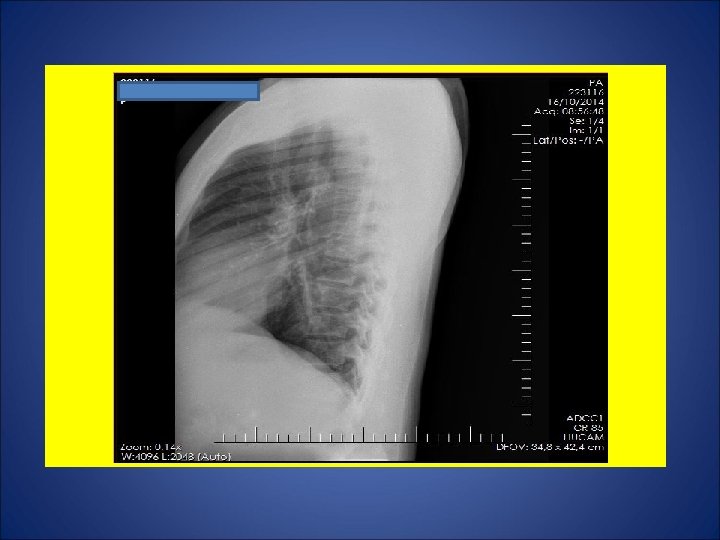

CASO 1: Paracoccidioidomicose em mucosa lingual diagnosticada por biópsia de lesão lingual em Fev/10, sendo iniciado STX-TMP 2 cp 12/12 h. Porém, fez uso irregular. Devido à não melhora clínica da lesão em queixo, o paciente foi internado em 09/out/14 para administração endovenosa de anfotericina B. Durante os últimos 2 -3 meses, relatou febre vespertina não aferida. Remissão da febre desde que internou. Tosse produtiva por 3 dias precedendo a sua internação em 09/out/14. Há mais ou menos 1 ano e meio, surgimento de lesão ulcerada em região inguinal direita próximo à bolsa escrotal. Regressão da lesão após introdução da anfotericina B. Lavrador (trabalhou em plantação de cana, milho, feno e carvoaria), mecânico (trabalhou em oficina de conserto de carro), pescador, servente de pedreiro. Negou contato com casos de tuberculose. Negou tuberculose prévia. Tabagista e etilista. HIV negativo. Ex. fisico: úlcera com várias crostas hemáticas em queixo acometendo o lábio inferior e as comissuras labiais, descorado (1+/4). Marca de BCG em MSD.

ESCARROS ESPONT NEOS: 1º) 20/10/14: 5 m. L – SALIVA – 1: 30 h: BAC NEG – TRM M. tuberculosis detectado - CULT em curso 2º) 21/10/14: 5 m. L – SALIVA – 30 min: BAC NEG – CULT em curso 3º) 22/10/14: 8 m. L – MUCÓIDE – 50 min: BAC NEG – CULT em curso